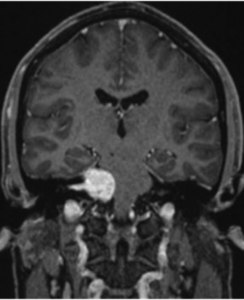

聴神経にできる良性腫瘍です。難聴やめまいが聴神経腫瘍の初期症状として現れることがあります。症状が突発性難聴と似ているため診断にはMRIが重要です。

脳腫瘍の初期症状としてめまいやふらつきが現れることがあります。めまいに加えて頭痛や吐き気、歩行時のふらつきや呂律が回らないといった神経症状を伴うことが多いです。

当院ではめまいの性状、起こり方などの病歴を丁寧に聴取し診察を行い、めまいの種類や分類を可能な限り見極めることを大切にしています。危険なめまい(脳梗塞や脳腫瘍)を除外する目的で必要があればMRI検査も行えます。